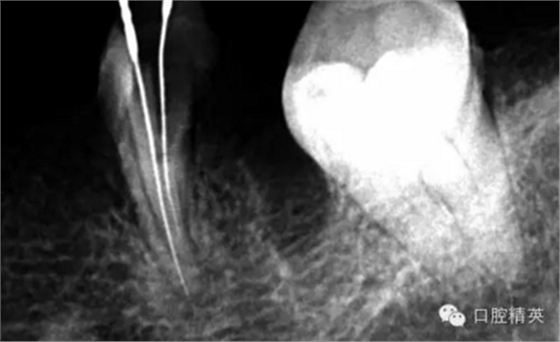

近中兩根試尖,預(yù)備根管15分鐘。

近中兩根根充。

這個(gè)也是我目前接到最有難度的器械分離病例,從片子上看近中器械分離兩節(jié),曾在外院做過干尸,有七年。當(dāng)看到這個(gè)病例時(shí)我沒有多大的把握,因?yàn)槲沂巧硖幓鶎?,無(wú)顯微,無(wú)放大。我只有抱著試一試的態(tài)度,但是她是我們?cè)簝?nèi)員工,壓力很大。

現(xiàn)在開始看第二張片子我疏通的遠(yuǎn)舌根,有點(diǎn)問題哦!~

根尖孔偏移,或者是片子角度問題,導(dǎo)致我們很難判斷,感覺像是測(cè)穿。但是我們有根測(cè)儀(前提它是好的),因?yàn)楦鶞y(cè)儀是我們目前對(duì)根管測(cè)量最具有說(shuō)服力,也是最為客觀事實(shí)的。根測(cè)儀沒有顯示一探入根尖下三分之一顯示“over”的情況(我用的是登士博根測(cè)儀)根管內(nèi)無(wú)滲出,可以測(cè)出根管的長(zhǎng)度。那就證明工作長(zhǎng)度的存在,和可信。在看看正題的近中根的器械,我想問問大家覺得是什么器械??

近中舌根疏通,兩根分離的器械都在近中舌根?;ㄙM(fèi)2個(gè)多小時(shí)。將它疏通下去還是離不開較長(zhǎng)的時(shí)間,也就是耐心,它真的很重要哦!~第二個(gè)我覺得器械分離的疏通,就是在于能否建立旁路,那么怎么去建立這條路。我個(gè)人覺得首先挫的選擇,是k挫,是c+,還是別的什么。我的首選是8號(hào)c+,因?yàn)樗鼔蛴玻?號(hào)的k挫太軟,沒有辦法擴(kuò)下去,很容易碰到根內(nèi)部器械導(dǎo)致器械報(bào)廢,尖端變光亮。但是c+挫也不是那么完美,我擴(kuò)的時(shí)候用了4根8號(hào)新的c+挫,全部報(bào)廢。尖端彎曲90度的,有變成麻花的。這些都在提醒我可能用力過大,或者根管內(nèi)部太過于復(fù)雜。疏通時(shí)只有慢慢來(lái),一點(diǎn)點(diǎn)的下千萬(wàn)不要妄想一步到位。手法還是要輕柔否則你的器械一樣也會(huì)分離進(jìn)去。疏通到挎自己的器械的時(shí)候也是碰到分離的器械時(shí),這個(gè)時(shí)候最好是上下提拉,切勿旋轉(zhuǎn)向下,你只有盡量將該部位擴(kuò)開,為下一步往下疏通留有足夠的空間就好。而不是繼續(xù)向下旋轉(zhuǎn),這樣會(huì)導(dǎo)致器械的分離,加大你疏通的難度。